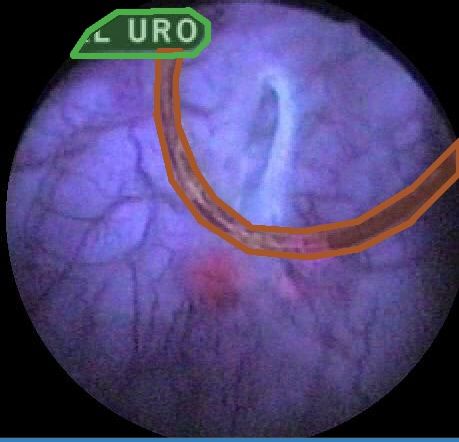

With the EAD Challenge we aimed to establish a first large and comprehensive dataset for “Endoscopy artifact detection” (see Fig. 1). The provided data was assembled from 6 different centers worldwide: John Radcliffe Hospital, Oxford, UK; ICL Cancer Institute, Nancy, France; Ambroise Parè Hospital of Boulogne-Billancourt, Paris, France; Instituto Oncologico Veneto, Padova, Italy; University Hospital Vaudois, Lausanne, Switzerland and the Botkin Clinical City Hospital, Moscow. This unique endoscopic video frame dataset is multi-tissue (gastroscopy, cystoscopy, gastrooesophageal, colonoscopy), multi-modal (white light, fluorescence, and narrow band imaging), is inter patient and encompasses multiple populations (UK, France, Russia, and Switzerland). Videos were collected from patients on a first-come-first-served basis at Oxford, with randomized sampling at French centres and only cancer patients were selected at the Moscow centre. Videos at these centres were acquired with standard imaging protocols using endoscopes built by different companies, Olympus, Biospec, and Karl Storz. The dataset was built randomly mixing the collected data with no exclusion criteria. All images have been carefully anonymised. No patient information should be visible in this data. A comprehensive open-source software222Useful tools for this dataset: https://sharibox.github.io/EAD2019/ have been established to assist the participants.

Examples for bounding box annotations for detection are shown in Fig. 2. It can be observed that while multiple boxes are annotated for several small specular areas; contrast, blur and instrument have relatively larger areas. Due to the overlap between two or more classes, the annotation by experts varied. This was minimized by following the detailed annotation protocol above. For semantic segmentation, a larger area mask was preferentially used to delineate locally very cluttered small specularity artifacts (see Fig. 3).